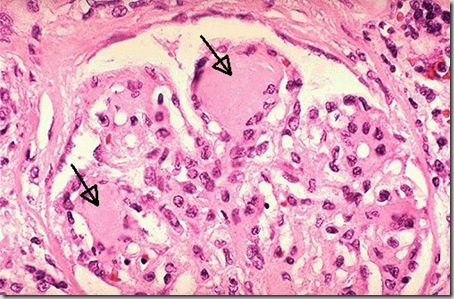

Microscopic section of kidney showing severe thickening of the glomerular basement membrane with the formation of Kimmelstiel-Wilson nodules.

Nodular glomerulosclerosis. This is the lesion of Kimmelstiel-Wilson disease

Histopathology of nodular glomerulosclerosis (Kimmelstiel-Wilson syndrome),